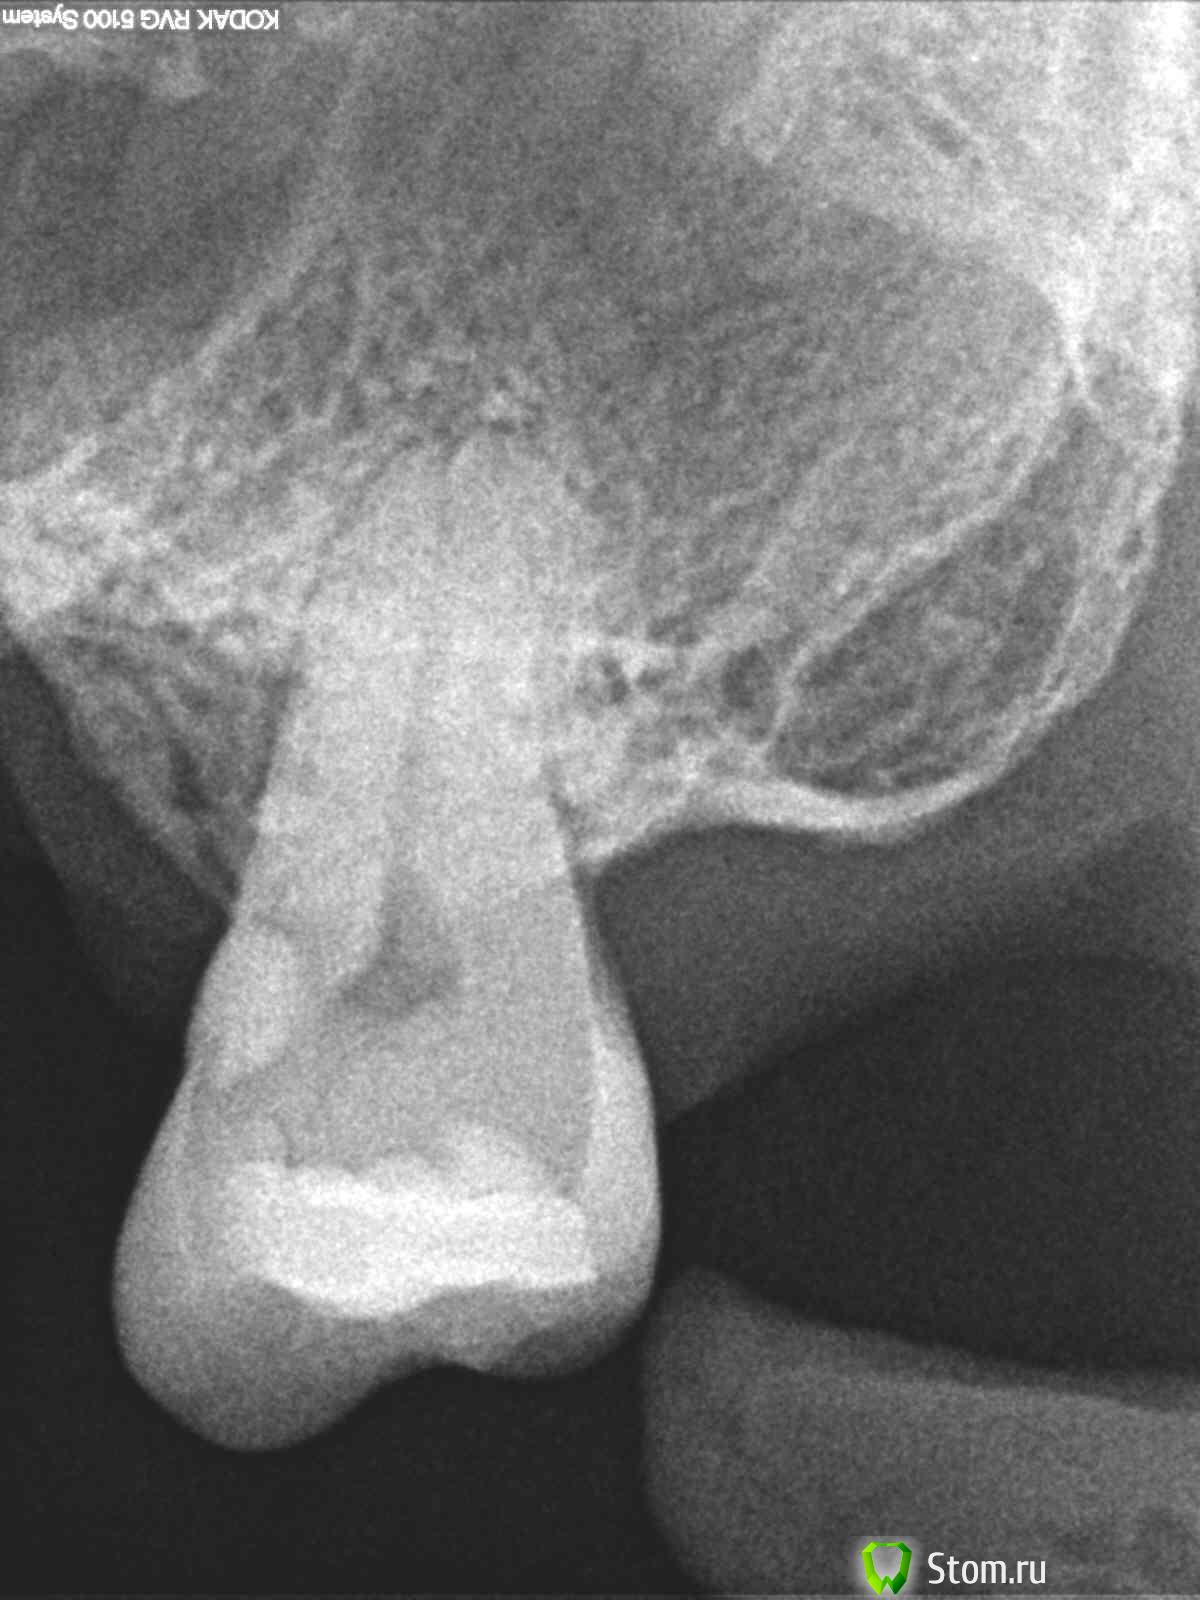

Практически 100% удаляю. Но... вот была ситуация - пациент 50 лет, носит съемный пластмассовый протез, зубов на в\ч мало, против имплантатов однозначно отказ (говорит, 10 лет назад пересаживали зубы...от трупа :blink: , через 5 лет все повываливались, больше ничего про имплантацию слышать не хочу). Пришел с чувствительностью 28 зуба на холодное, зуб является опорой кламмера протеза. По снимку - глубоко. Стала снимать пломбу с медиальной поверхности - вскрыла полость зуба. Отправила на КТ с условием - если каналы "нормальные", будем лечить, если нет - удалять, хотя в принципе по прицельному виден 1 канал прямой, но с КТ надежнее.

На КТ - один прямой широкий канал, пац рот открывает хорошо, полечили

В принципе удалить 28 и пределать съемник он всегда успеет.

Но если б каналы были "кудрявые" браться за зуб вряд ли стала, почувствую себя героем в чем-нибудь другом :)